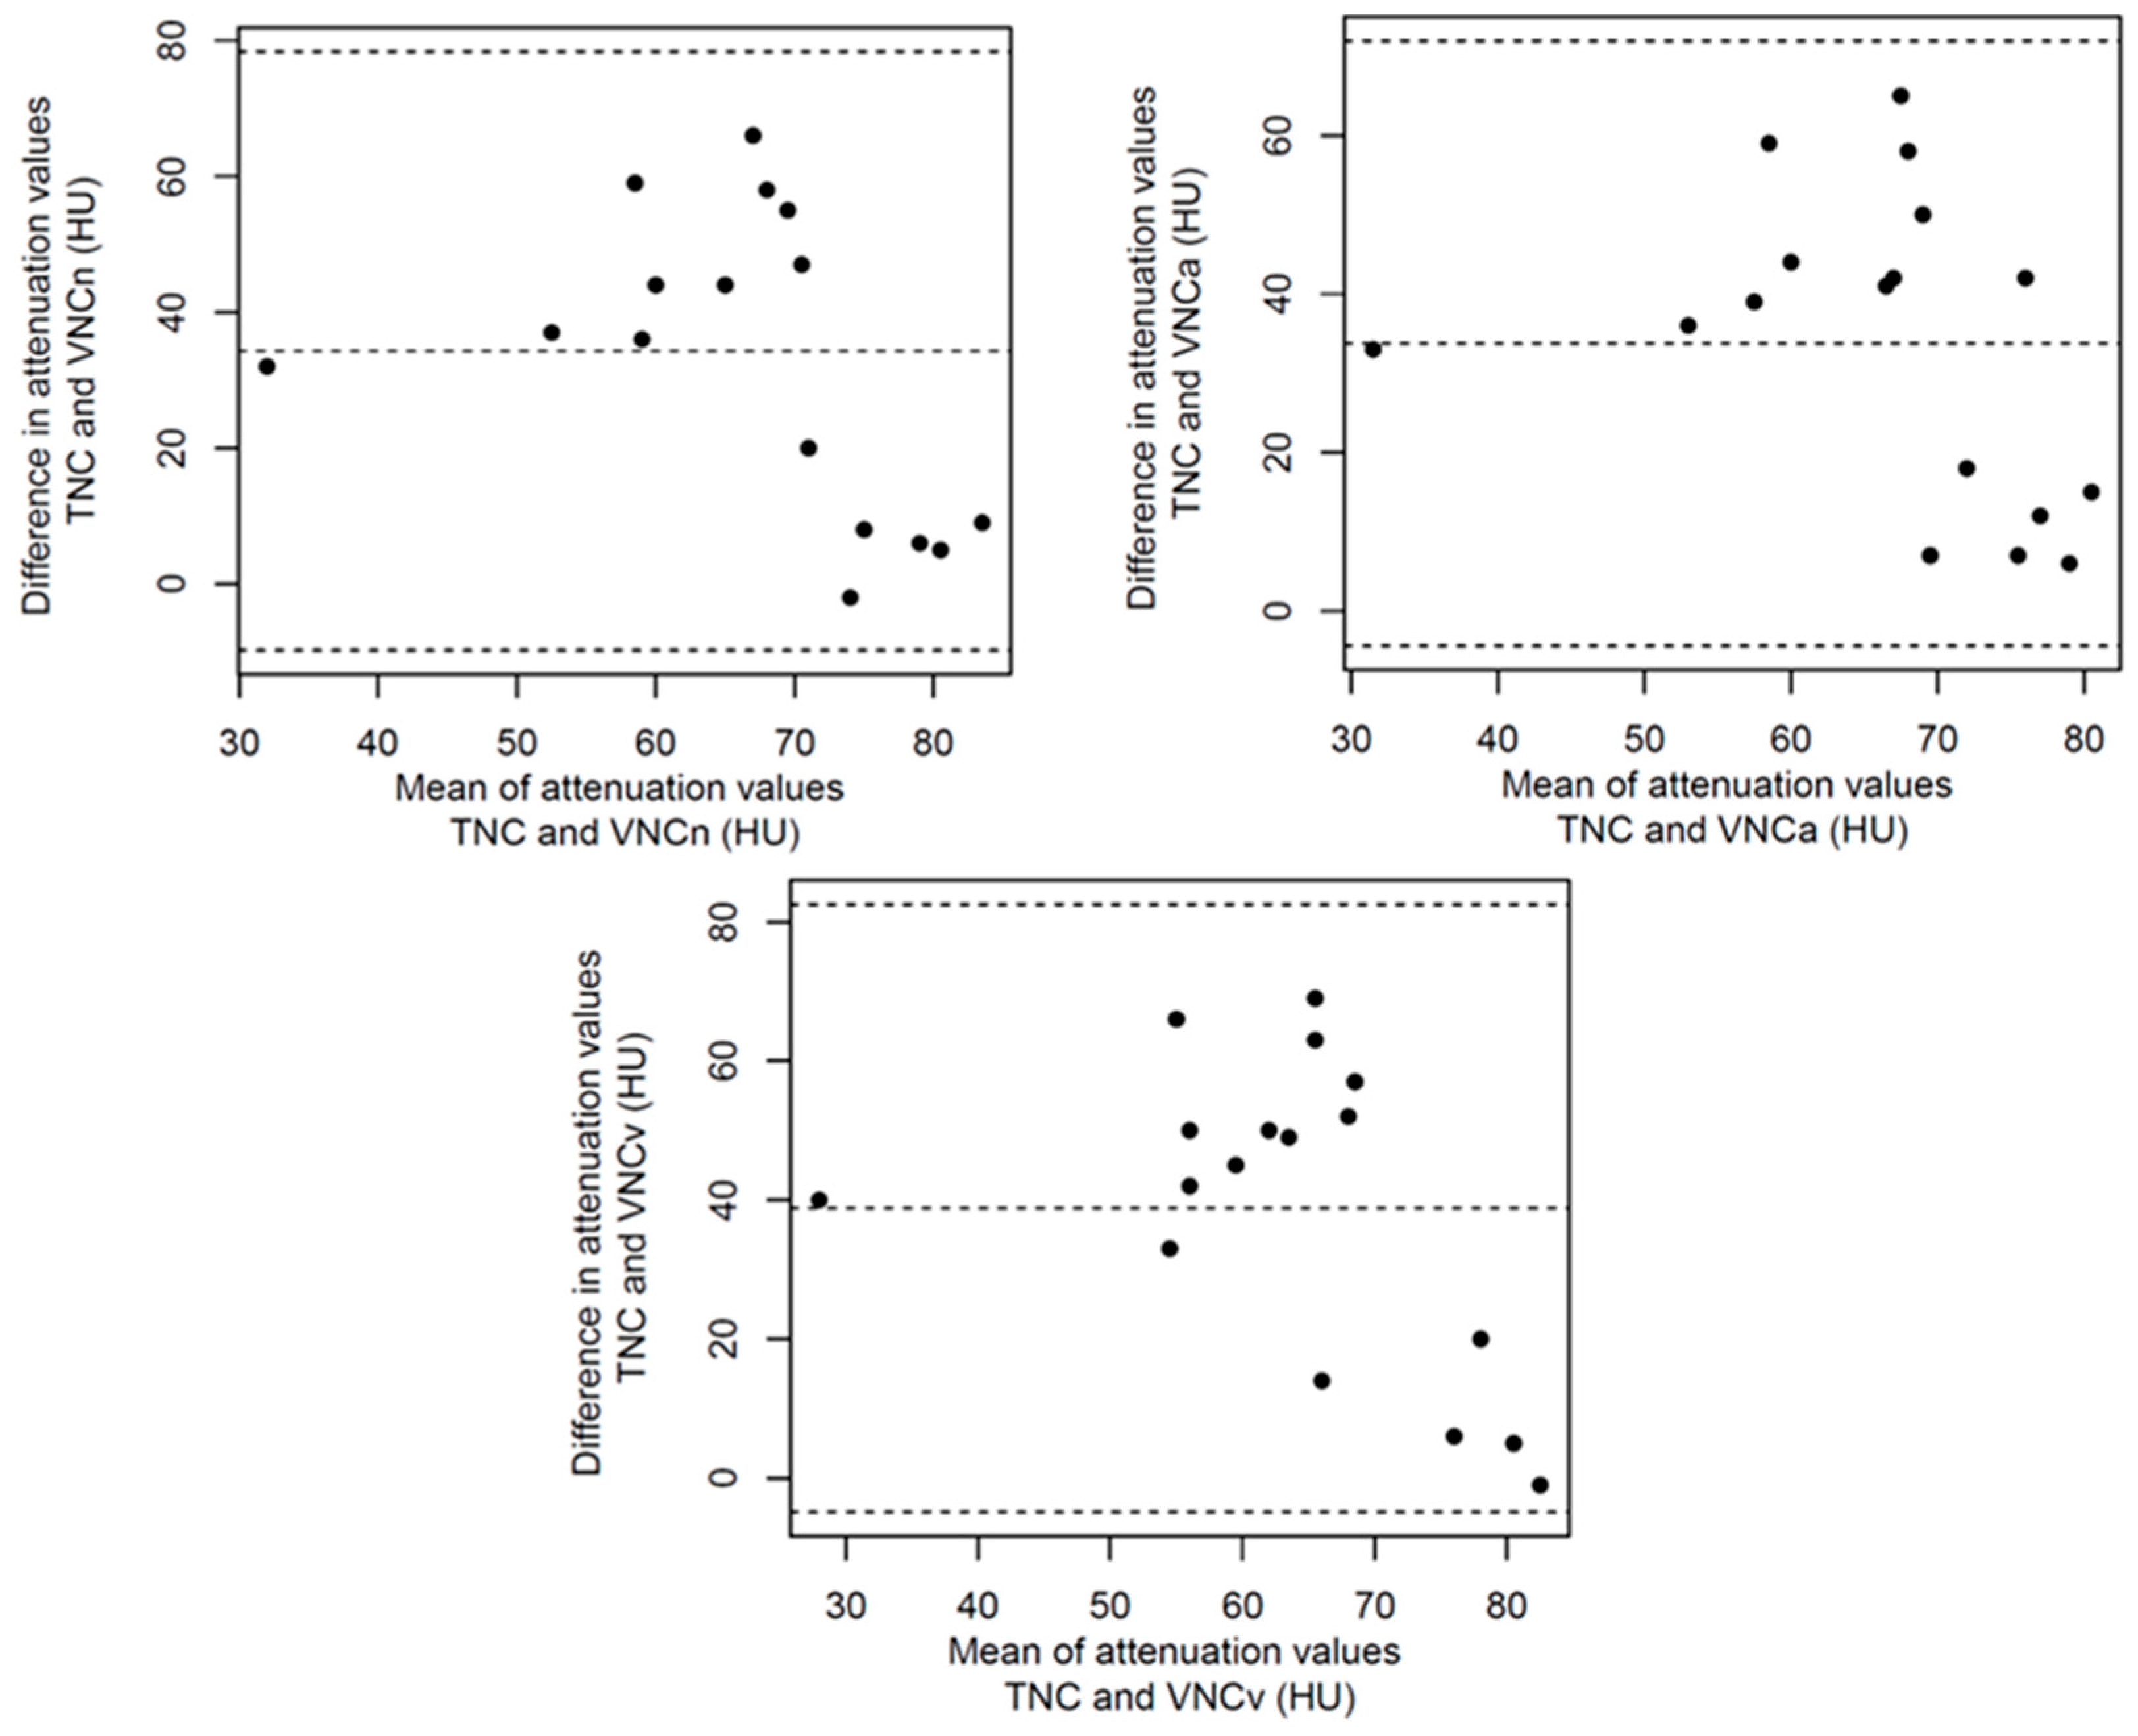

3.2. Structured Measurement